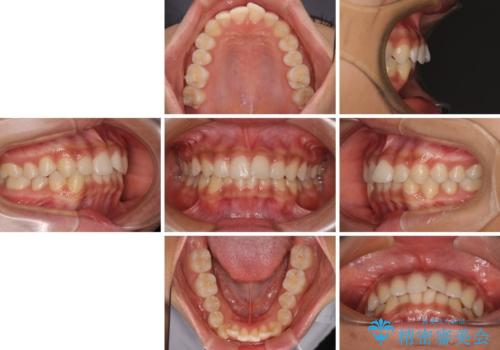

- 上下前歯の叢生を気にして来院された患者様です。

インビザラインでの治療を希望されていて、デコボコの程度が中等度であり、安価なパッケージにて対応可能と判断されたため、インビザライン・モデレートを用いて矯正治療を行うこととしました。

インビザライン・モデレートは、製作できるアライナーの枚数に制限があるため、移動可能な量に限りがあるものの、インビザライン・ライトよりも枚数が多いため、幅広い症例に対応可能です。